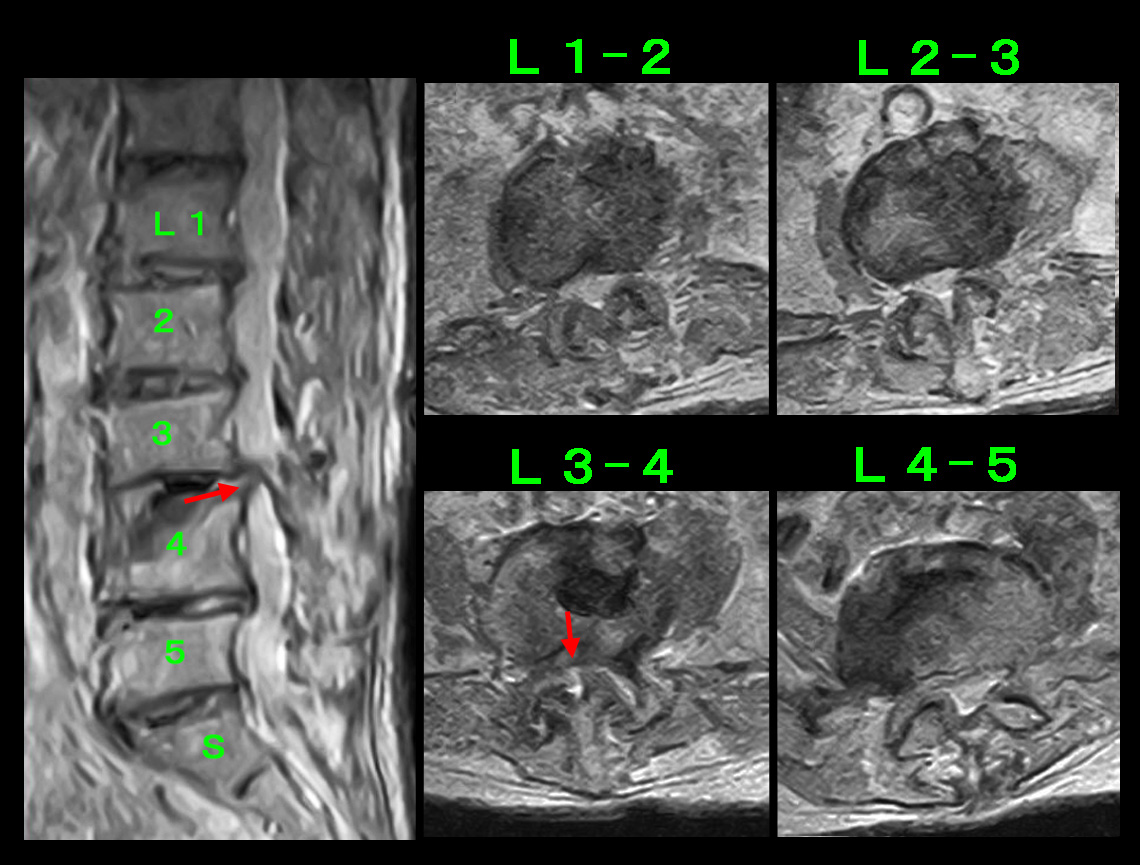

腰椎MRI検査では、L3-4とL4-5に軽度の椎間板ヘルニアを認めますが、中央上段のT1矢状断の右よりの画像でL3-4のヘルニアの方がL4-5のヘルニアより白っぽく目立ちます。これはL4-5ヘルニアが最近悪化したことを示す所見です。股関節痛は坐骨神経痛ととらえられるので、おそらく服薬では症状の軽減がえられないため、神経根ブロックを勧めましたが、患者さんは希望されませんでした。そのため鎮痛剤と筋弛緩剤を1週分処方しました。